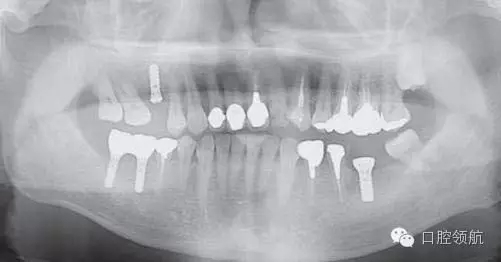

圖2是右側(cè)種植體植入后,左下磨牙缺損部診斷用導(dǎo)板戴用時的曲面斷層影像。拔牙后6個月,在預(yù)定植入部位有若干不透明的影像。

圖2 左下磨牙缺損部植入前的曲面斷層影像。